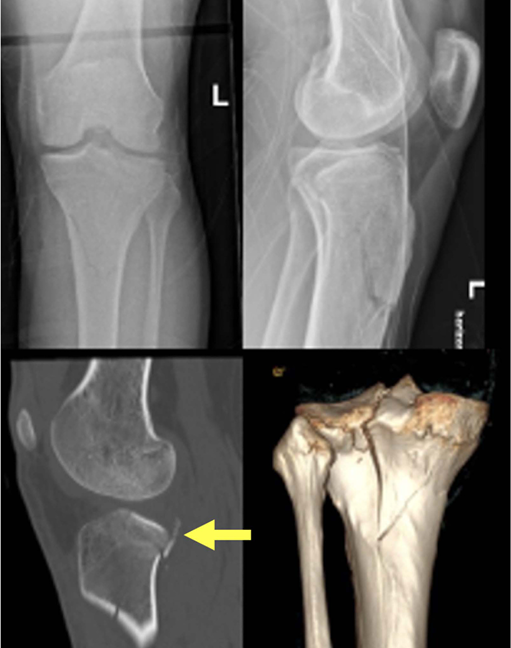

病例展示:后外侧劈裂塌陷骨折(Kfuri-Schatzker type II P型),A. 入院X线片,B. CT三维重建:清晰显示一个延长的后外侧劈裂骨块(星号标注)。此形态学分类有助于理解骨折的稳定性和手术策略。C. Carlson入路手术步骤:患者俯卧位,切口略偏内侧,与腓骨走向平行。神经显露:腓总神经(星号标注)位于浅筋膜下方、腓肠肌外侧头外侧,易于辨识。深层显露:将比目鱼肌从腓骨上剥离并抬起。将腘肌向内侧牵开。此时可显露外侧半月板(#号标注)。关节内观察:将外侧半月板向近端牵开后,可见后外侧缘的粉碎情况。